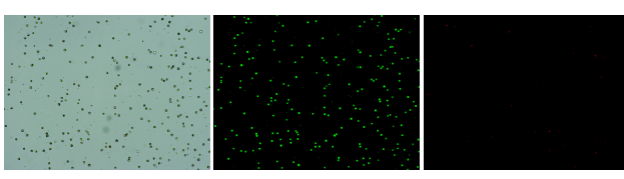

人膽管癌樣本,活性90.45%,結(jié)團(tuán)率7.2%